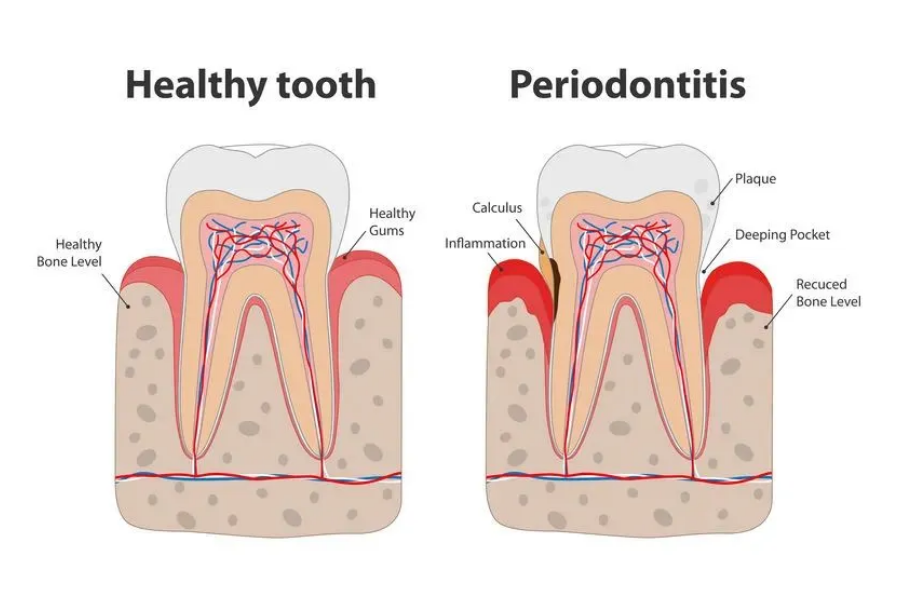

1、炎症性牙龈萎縮

炎症性牙龈萎縮是(shì)比較常見(jiàn)的(de),一(yī)般是(shì)牙周炎 ₽導緻牙周組織遭到(dào)破壞引起萎縮,使附著(zhe)在牙槽骨上≠©(shàng)的(de)牙龈也(yě)随著(zhe)向牙根方向萎縮,多≥ε✘←(duō)發生(shēng)于有(yǒu)牙周炎的(de)★∏人(rén)。